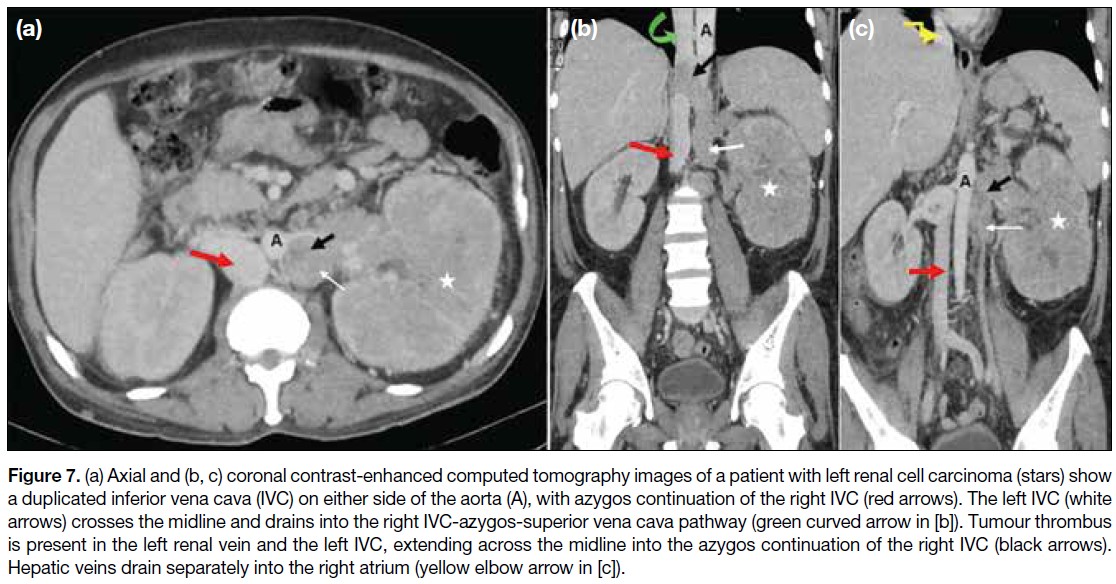

Figure 7. (a) Axial and (b, c) coronal contrast-enhanced computed tomography images of a patient with left renal cell carcinoma (stars) show

a duplicated inferior vena cava (IVC) on either side of the aorta (A), with azygos continuation of the right IVC (red arrows). The left IVC (white

arrows) crosses the midline and drains into the right IVC-azygos-superior vena cava pathway (green curved arrow in [b]). Tumour thrombus

is present in the left renal vein and the left IVC, extending across the midline into the azygos continuation of the right IVC (black arrows).

Hepatic veins drain separately into the right atrium (yellow elbow arrow in [c]).